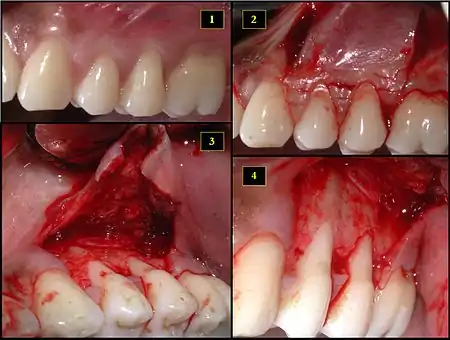

Subepithelial connective tissue graft

- Recipient site exhibits gingival recession on both premolars and first molar (molar recession is not an esthetic issue and will not be treated)

- Incisions prior to flap reflection

- Full thickness flap elevated

- Another viewpoint of the flapped recipient site